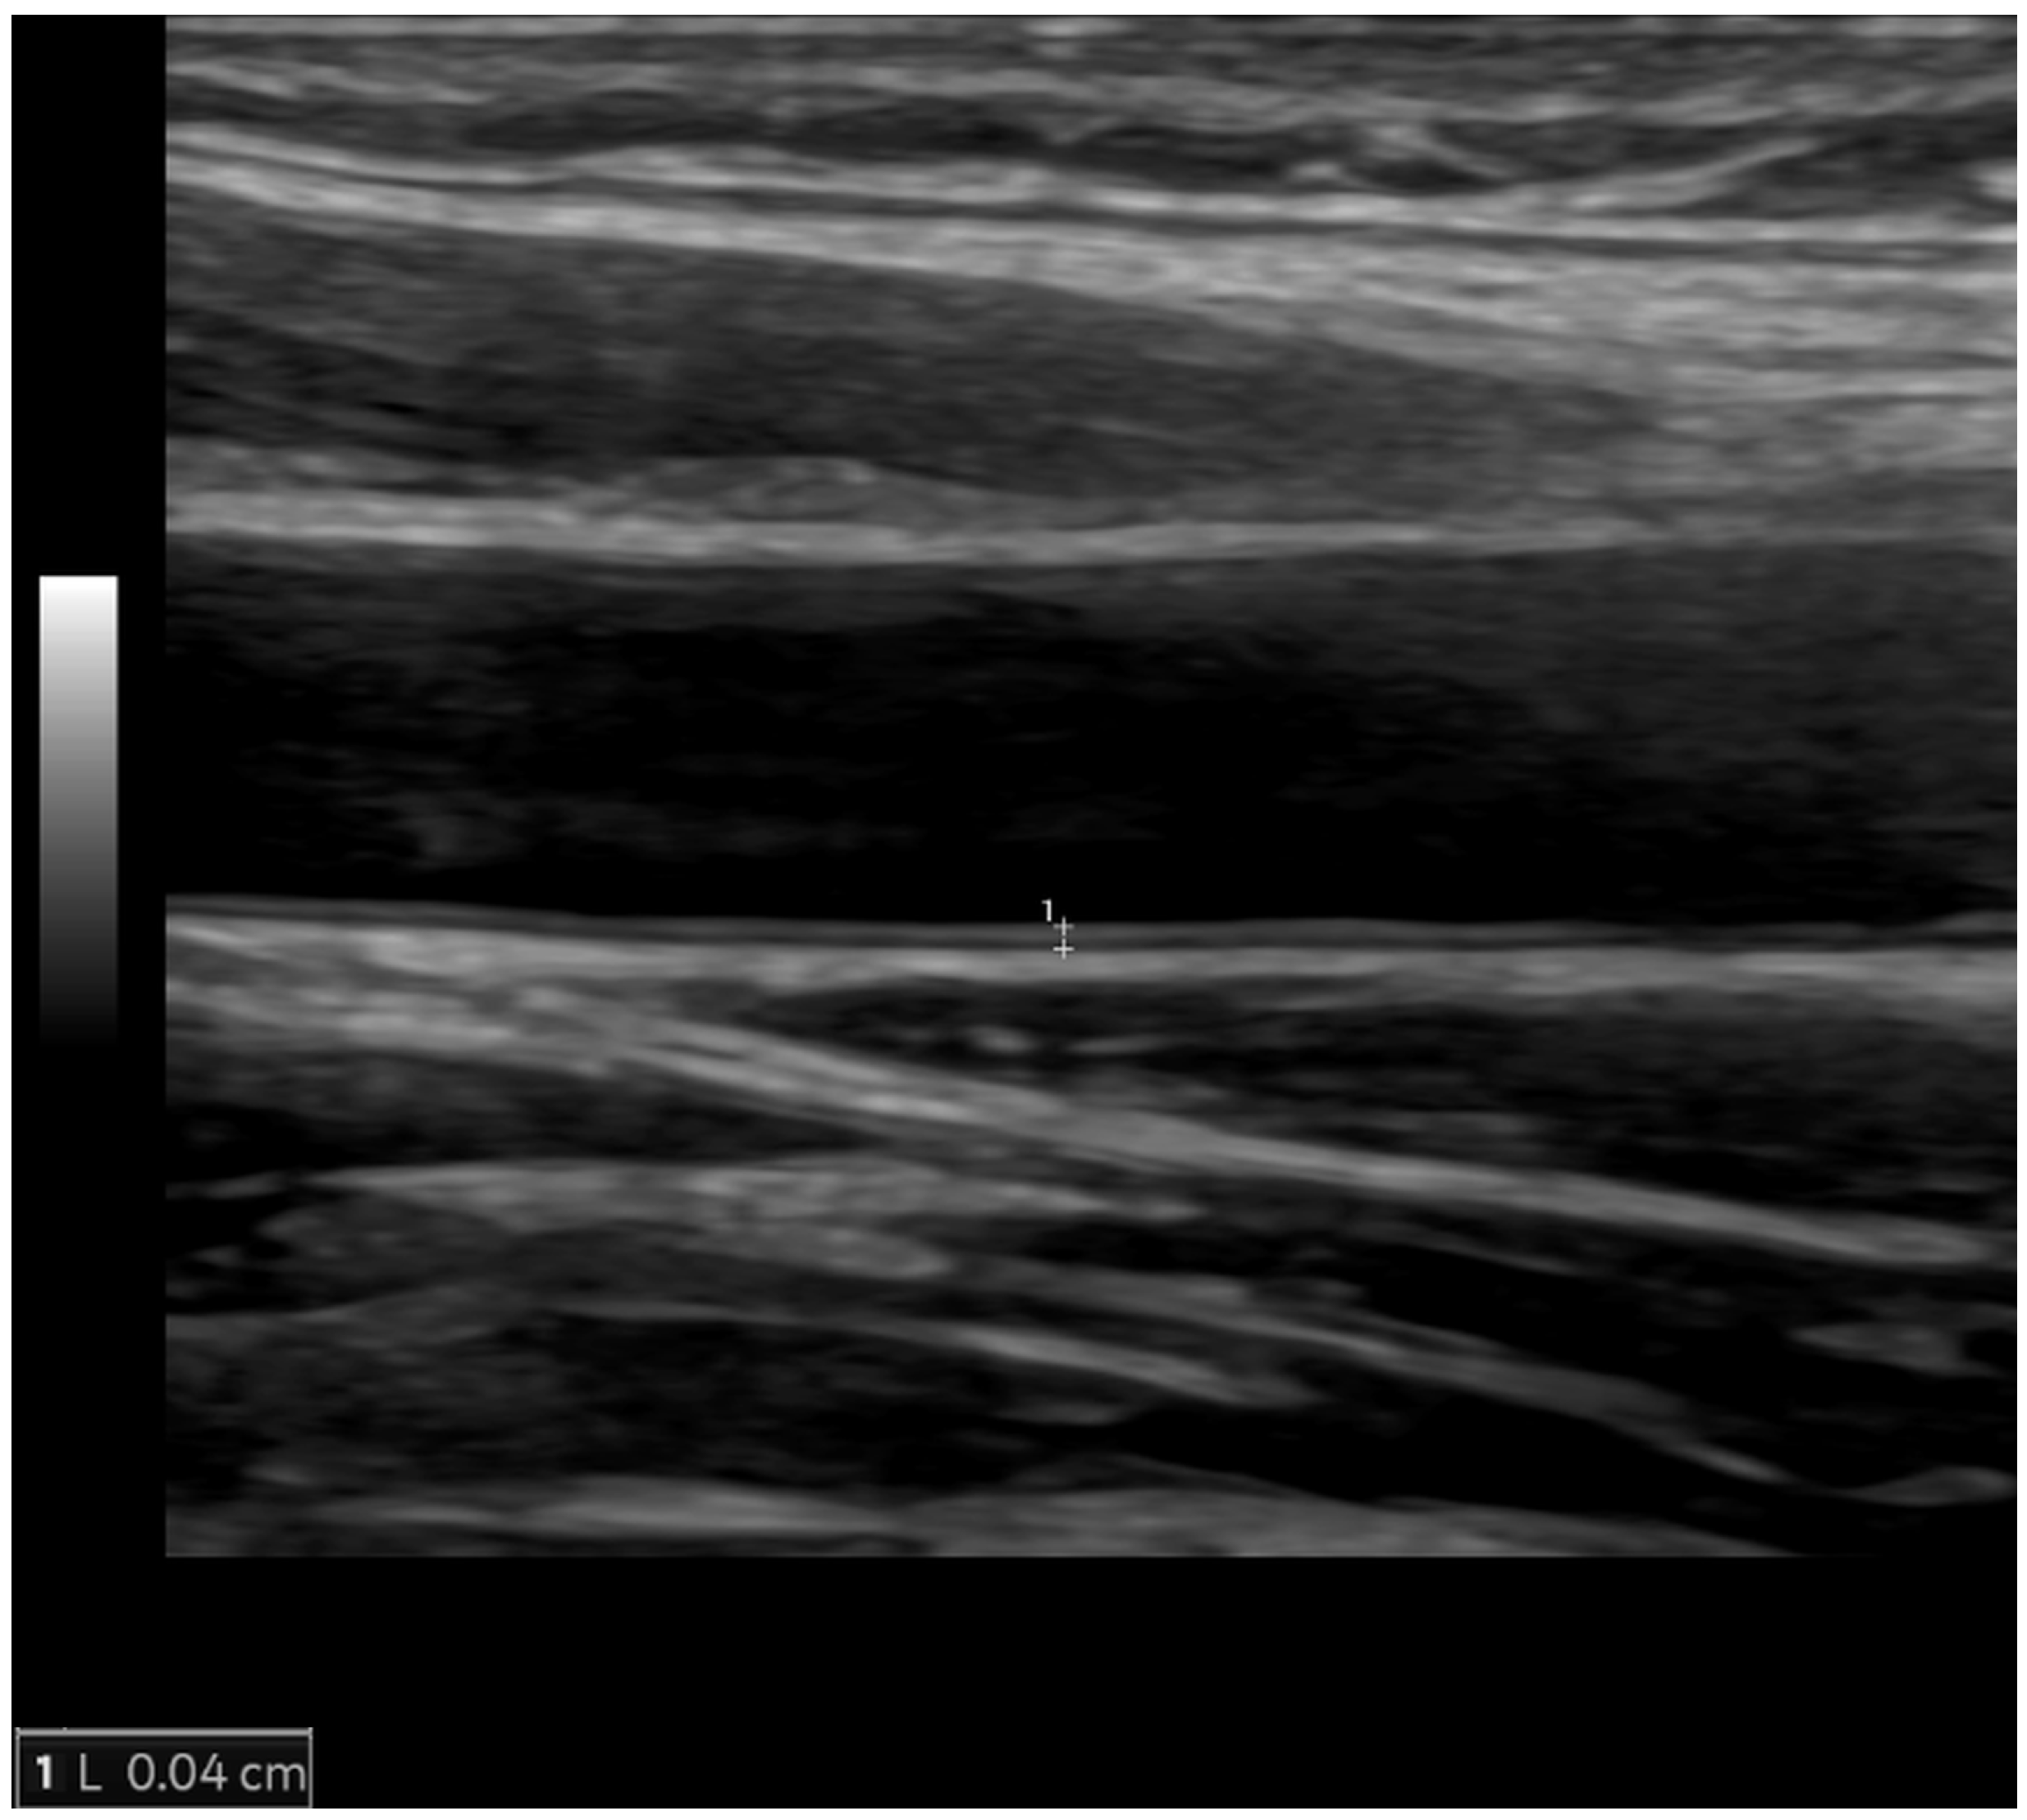

5.1. Ultrasonography and Echocardiography

| Vascular aging | |

| Arterial wall thickening | Increased carotid intima-media thickness |

| Arterial wall stiffening | Reduced aortic strain and distensibility, increased pulse–wave velocity |

| Ultrasonography and echocardiography | Carotid imaging (carotid intima-media thickness, atherosclerotic plaques) Cardiac morphology and function Aortic stiffness (pulse wave velocity, aortic strain, and distensibility) | First-line imaging modality for assessment of carotid arteries First-line imaging modality for cardiac morphology and function assessment | Inexpensive Easily available Portable No ionizing radiation | Limited acoustic window Very limited possibilities for myocardial tissue characterization |